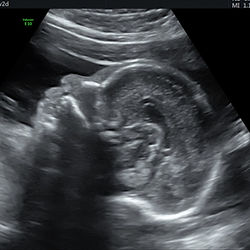

İkinci Trimester Muayenesi

18-24. gebelik haftaları arasında bebeğinizin ultrasonografi ile büyüklüğü, organ gelişimi, gebelik sırasında ortaya çıkabilecek gebelik hipertansiyonu, erken doğum gibi sorunların ön bulgularının ortaya çıkıp çıkmadığını araştırmak için yapılan muayenedir.